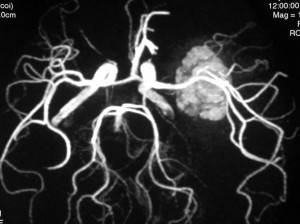

脳血管撮影の静脈層です。 血管腫の内側に刷毛で掃いたような異常な静脈が見えます。これは静脈性血管腫といって,大きな海綿状血管腫にはよく合併する異常です。海綿状血管腫をとるときに誤ってこの静脈性血管腫を傷つけてしまうと,静脈梗塞が起きるので注意しなければなりません。このケースの場合はもし損傷すると左側頭葉内側の脳損傷になります。